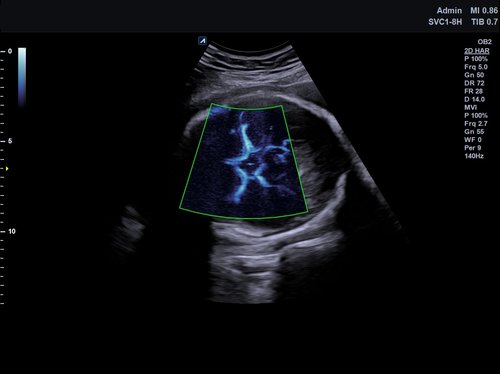

Das X-CUBE 70 fügt sich nahtlos in die neue X-CUBE Serie ein. Wie bereits das X-CUBE 90 so nutzt auch das X-CUBE 70 Farbdopplersystem die Bildverarbeitungstechnologien eines Premiumsystems, eine Vielzahl neuer Breitband-Schallköpfe mit X+ Crystal SignatureTM Technologie und neuen technischen Raffinessen.

Das X-CUBE 70 bietet modernste Technologien für eine objektive und akkurate Diagnose. Intelligente klinische Module heben das System auf ein neues diagnostisches Niveau. Es erweitert Ihre Fähigkeiten und die Bandbreite Ihrer Möglichkeiten. Dazu gehören Module wie MicroView, point Shear Wave Elastographie (pSWE), oder auch die Kontrastmittelsonographie.

• SVC1-8H (1-8 MHz) für Ultraschalluntersuchungen in Bereichen Abdomen, Geburtshilfe, Gynäkologie, Urologie, Pädiatrie, EM